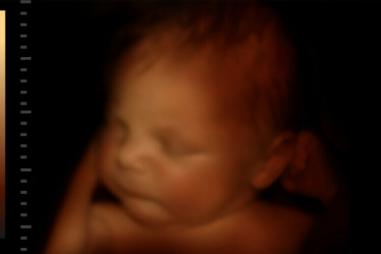

Kultúra života

Nenarodené dieťa sa usmieva po tom, čo počas ultrazvuku počulo hlas otca

03.10.2024 BRA

Virálne video nenarodeného dieťaťa, ktoré reaguje na hlas svojho otca, poukazuje na krásu a ľudskosť nenarodených detí. Na videu, ktoré nahral denník New York Post, je vidieť, ako sa 32-týždňové…